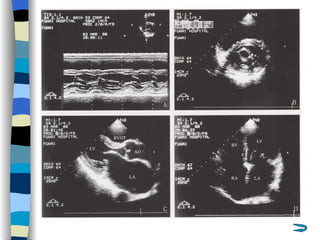

Echocardiography The most valuable technique for diagnosing MS, and determining its severity M-mode echo : Thickened, calcified leaflets open poorly, close slowly (EF slope ↓ ) The double peaks disappear Both leaflets move anteriorly during early diastole Two-dimensional echo: Fusion, thickening,  doming  of the valve leaflets, and poor leaflet separation in diastole;  mitral orifice area ↓

Doppler echo : Most accurate noninvasive technique for quantifying the severity of MS Spectrum Doppler: measure transvalvular gradient, MVA Color Doppler: display  high velocity color jet Provide other important information Cardiac chamber size (LA, RV) Left ventricular contractility Pulmonary arterial pressure Other coexisted valvular or congenital abnormalities  Mural thrombi